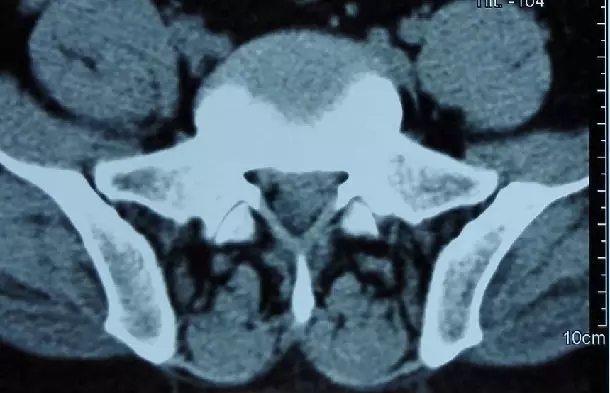

(磁共振和CT椎间盘脱出)

(椎间盘脱出)